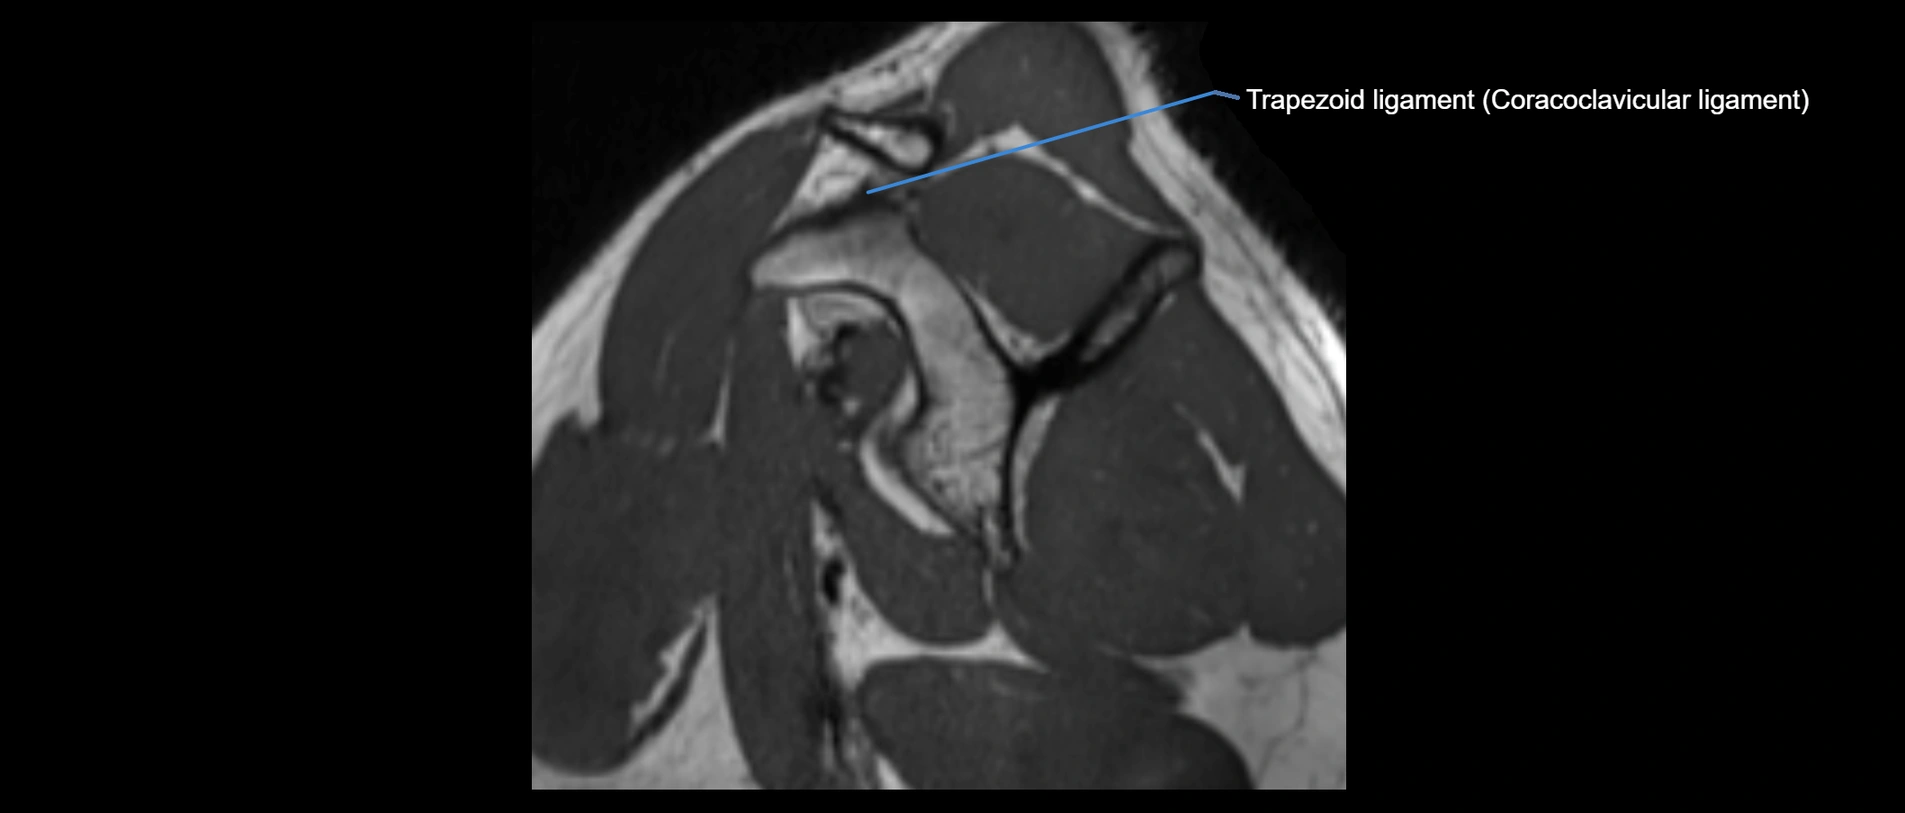

CT image

image